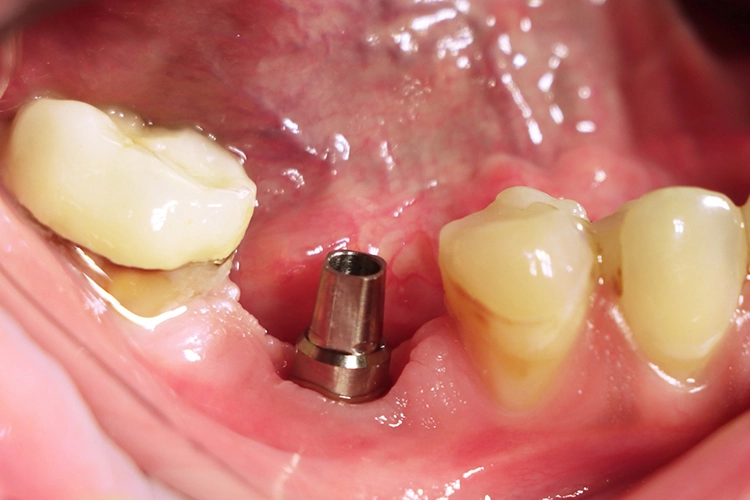

Im nächsten Schritt erfolgte die vollständig navigierte Implantation des Microcone-Implantates (Ø 5,0 mm, 9 mm Länge) in der Region 46 (Abb. 8-14) nach dem vom Hersteller empfohlenen Bohrprotokoll, das sich nach Knochenqualität und Implantatdurchmesser richtet. Die Chirurgie-Kassette (Abb. 6) ist übersichtlich aufgebaut und intuitiv zu bedienen. Zur schonenden Präparation des knöchernen Implantatbetts stehen je nach Implantatdurchmesser und Knochenqualität bis zu fünf verschiedene Bohrertypen mit Farbcodierung zur Verfügung. Das Implantat war für eine gedeckte Einheilung vorgesehen und der Kieferkamm wurde durch Nahtlegung speicheldicht verschlossen (Abb. 15).

Die Dokumentation des Implantatsitzes erfolgte mit einer postoperativen Panoramaschichtaufnahme (Abb. 16). Nach der gedeckten Einheilung erfolgte im Juni 2021 die geschlossene Implantatabformung mit Impregum. Abbildung 17 bis 25 zeigt den Ablauf von der Inzision drei Monate nach Implantation bis zum Einsetzen des Hybrid-Abutments mit Titan-Klebebasis und Zirkonaufbau bis zur finalen Zirkonkrone, die aufgrund einer Erkrankung der Patientin etwas später als vorgesehen im Juli 2021 eingegliedert werden konnte. Die Versorgung der insuffizienten Einzelkrone 47 erfolgt auf Patientenwunsch zu einem späteren Zeitpunkt.